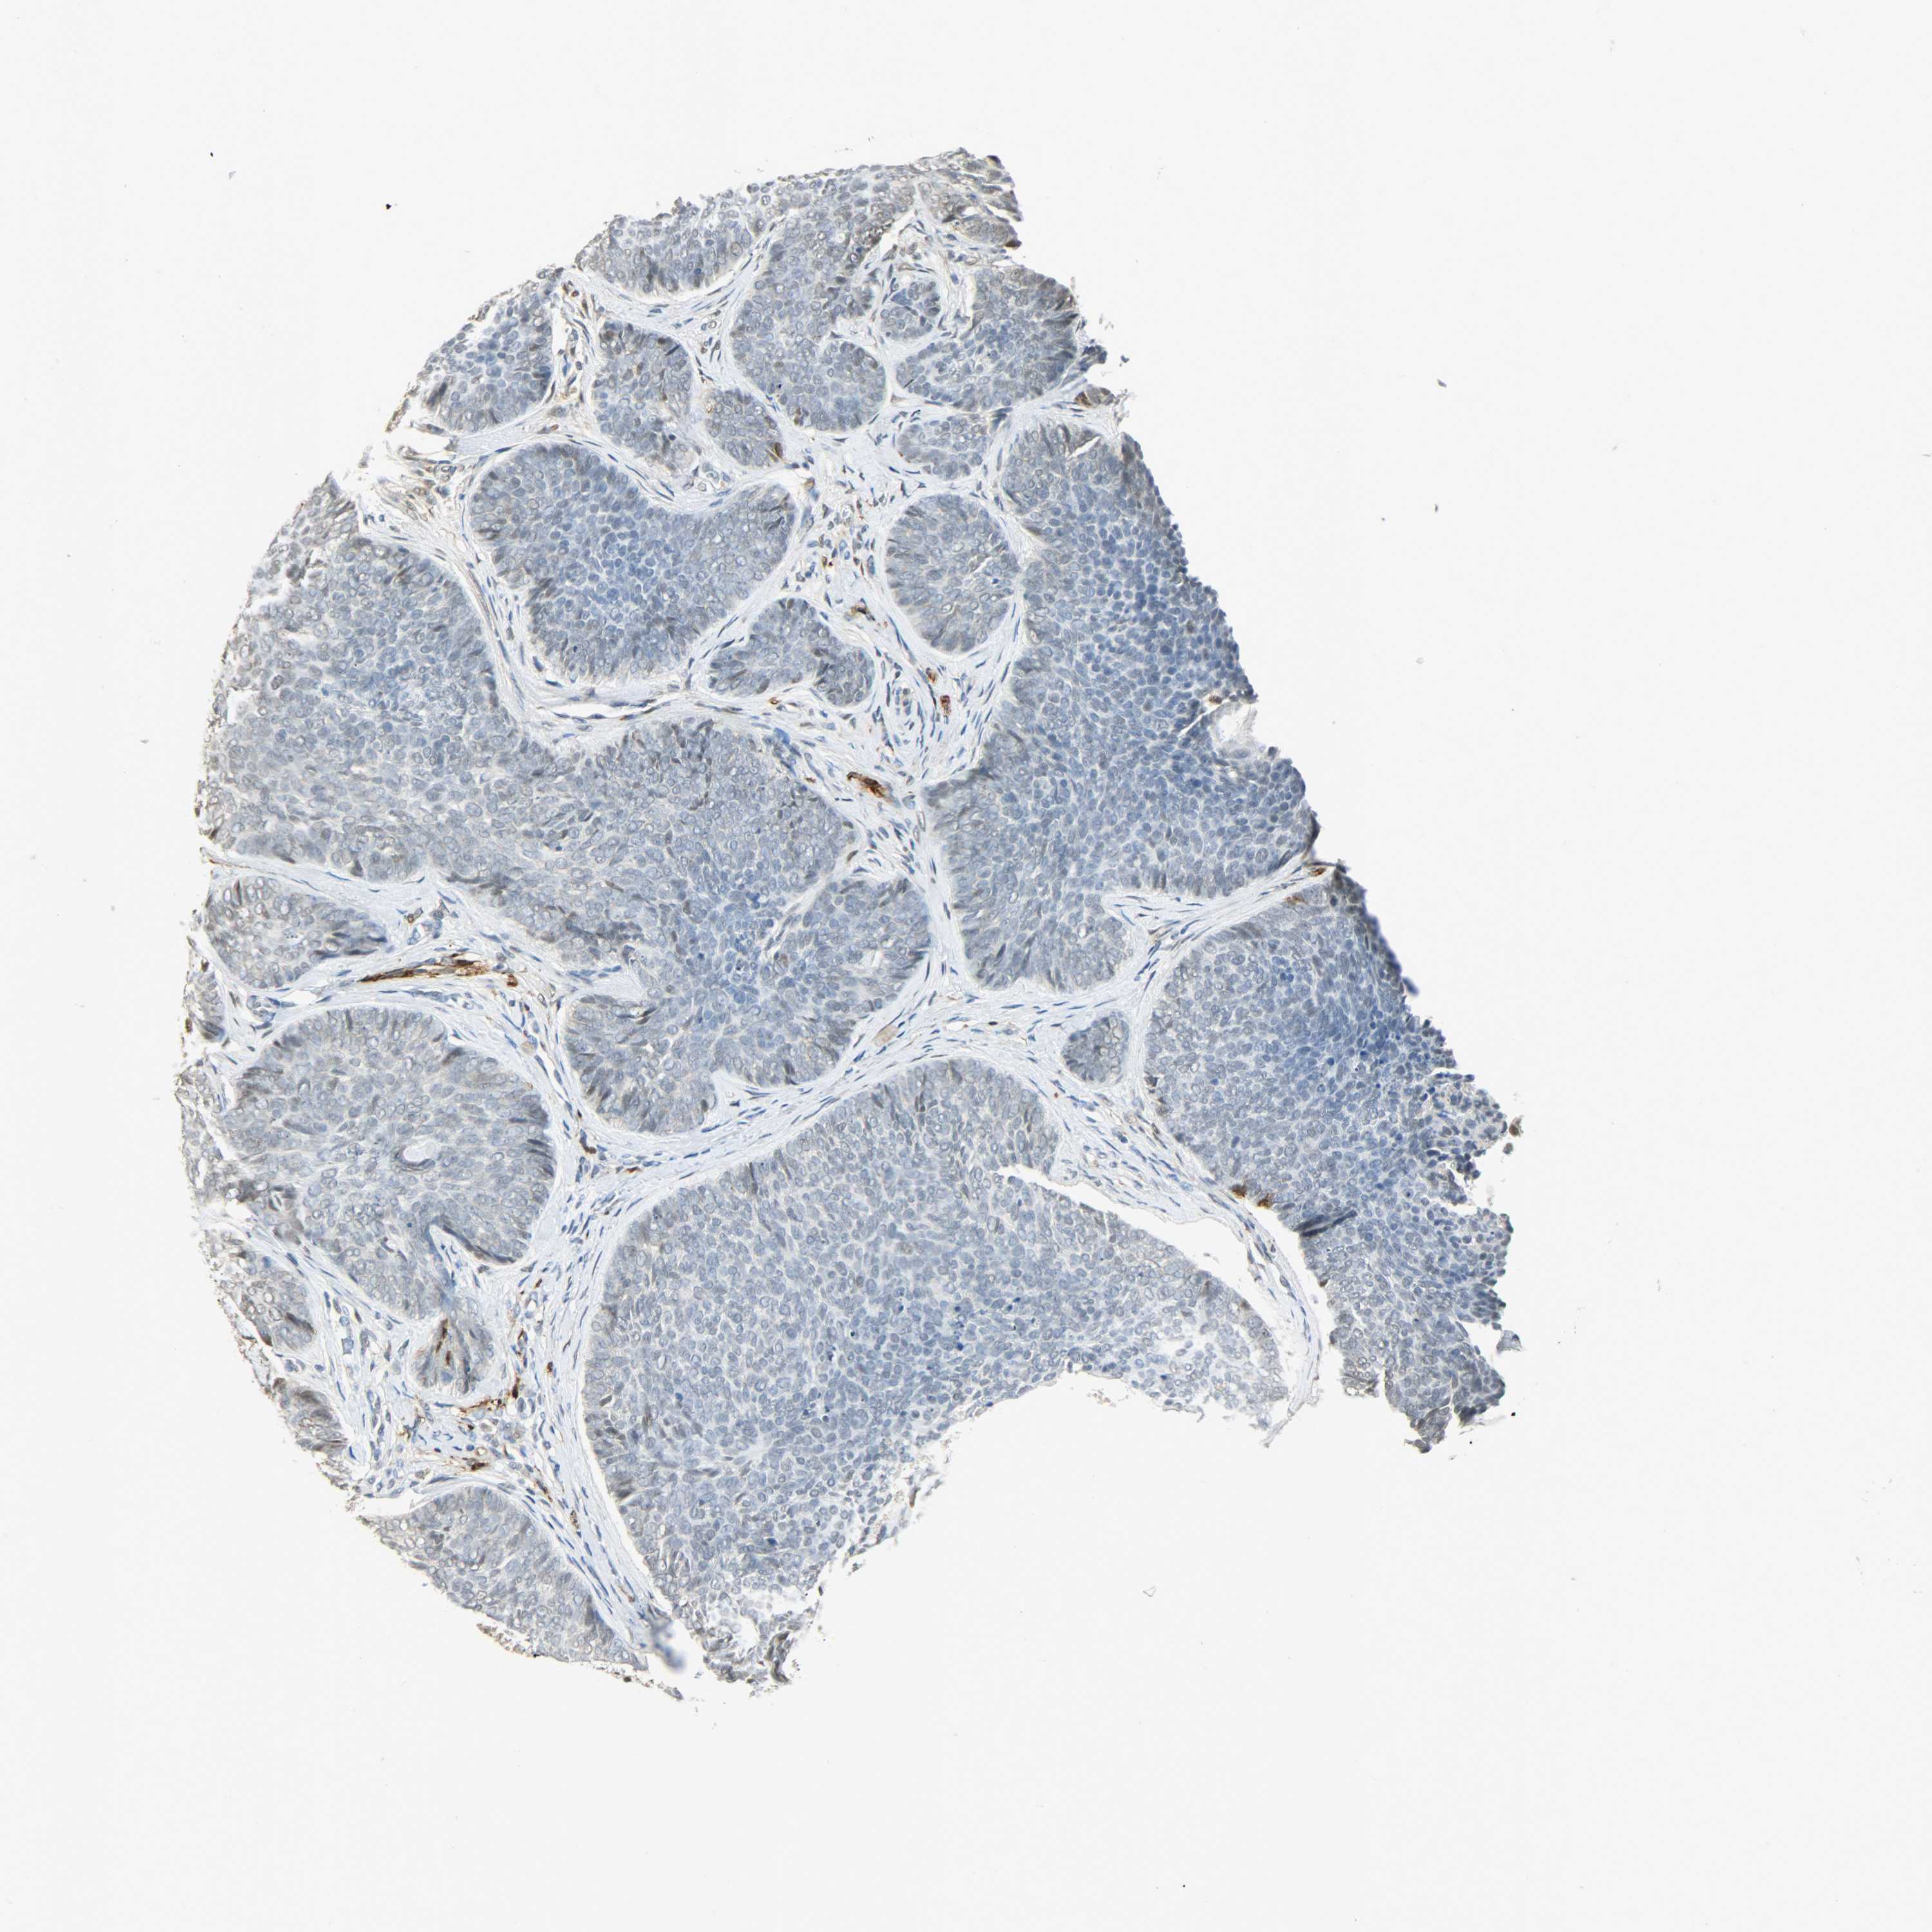

SKIN CANCER - Protein expressioni

A mouse-over function shows sample information and annotation data. Click on an image to view it in a full screen mode. Samples can be filtered based on level of antibody staining by selecting one or several of the following categories: high, medium, low and not detected. The assay and annotation is described here.

Antibody staining in the annotated cell types in the current human tissue is reported as not detected, low, medium, or high, based on conventional immunohistochemistry profiling in selected tissues. This score is based on the combination of the staining intensity and fraction of stained cells.

Each image is clickable and will lead to virtual microscopy that enables deeper exploration of all samples and also displays staining intensity scores, fraction scores and subcellular localization as well as patient and tissue information for each sample.

Antibody CAB000143

Basal cell carcinoma